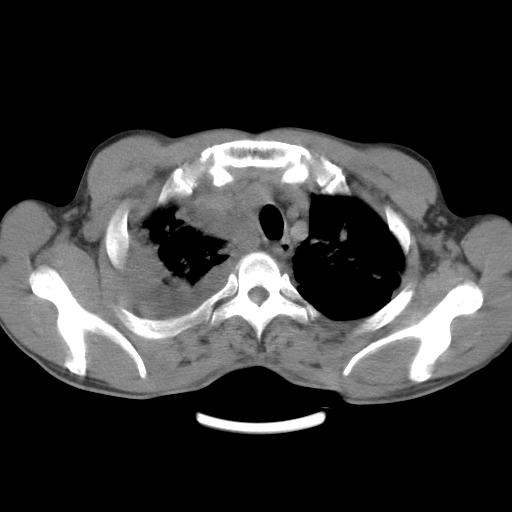

男性,44岁,结核病史多年。现胸闷气短,咳嗽,偶咳血。

1、右侧大量胸腔积液伴右肺压缩性膨胀不全,建议抽液治疗后复查 2、两肺继发性tb伴空洞形成。

1)两肺继发性肺结核伴空洞形成,左肺多发性结核球。2)右侧大量胸腔积液伴右肺部分膨胀不全。3)纵隔淋巴结肿大。

1,双肺多发结节 并空洞影改变, 左侧胸腔积液并部分包裹, 结合原病史首先考虑结核. 但也不除外其它.

2,左侧有一根肋骨陈旧性骨折? 建议追查 .